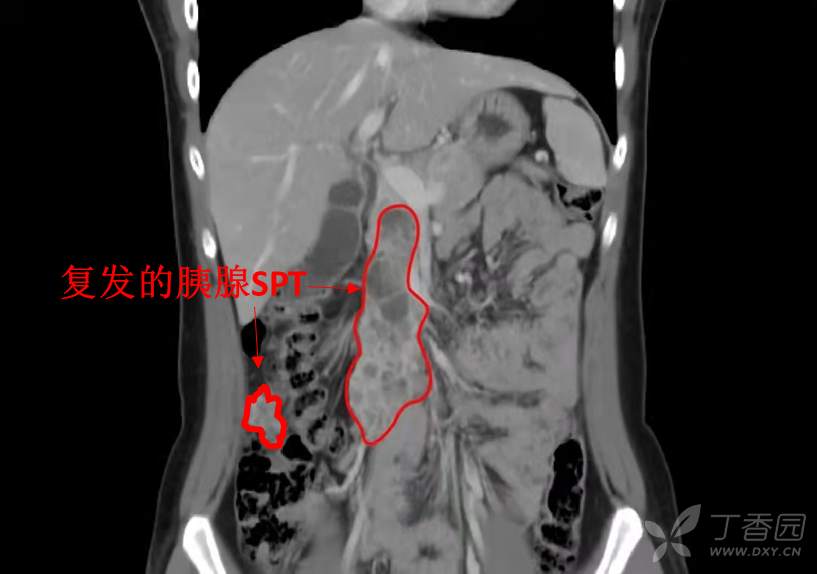

术前检查:化验无特殊,影像检查如下图,复发的胰腺实性假乳头状瘤压迫浸润了很长一段SMV,腹腔内还有散在复发病灶。

术中探查发现胰头后方见大小不等的囊实性肿块融合,向上与胆总管右侧壁结节延续,向下与结肠系膜延续,后方与下腔静脉前壁粘连较重……见胰头下缘及钩突大小不等囊实性肿块融合成“串珠样”向下延续,浸润横结肠系膜血管无法分离,触及肠系膜上静脉上段已被肿瘤浸润无法分离显露。好的一点是肠系膜上动脉主干可分离,未受肿瘤侵犯。

考虑胰头肿瘤向下明显浸润肠系膜上静脉主干及横结肠系膜静脉主干,门静脉及脾静脉汇合部良好,故决定沿脾静脉汇入门静脉处下缘处以血管阻断钳夹闭肠系膜上静脉并切断,于肠系膜上动脉起始部远端2厘米处以血管阻断钳夹闭并切断,于回盲部近端20厘米处离断末端小肠,整块移去切除的肿瘤所在胰头体部和钩突、肝外胆管、十二指肠及全部小肠。